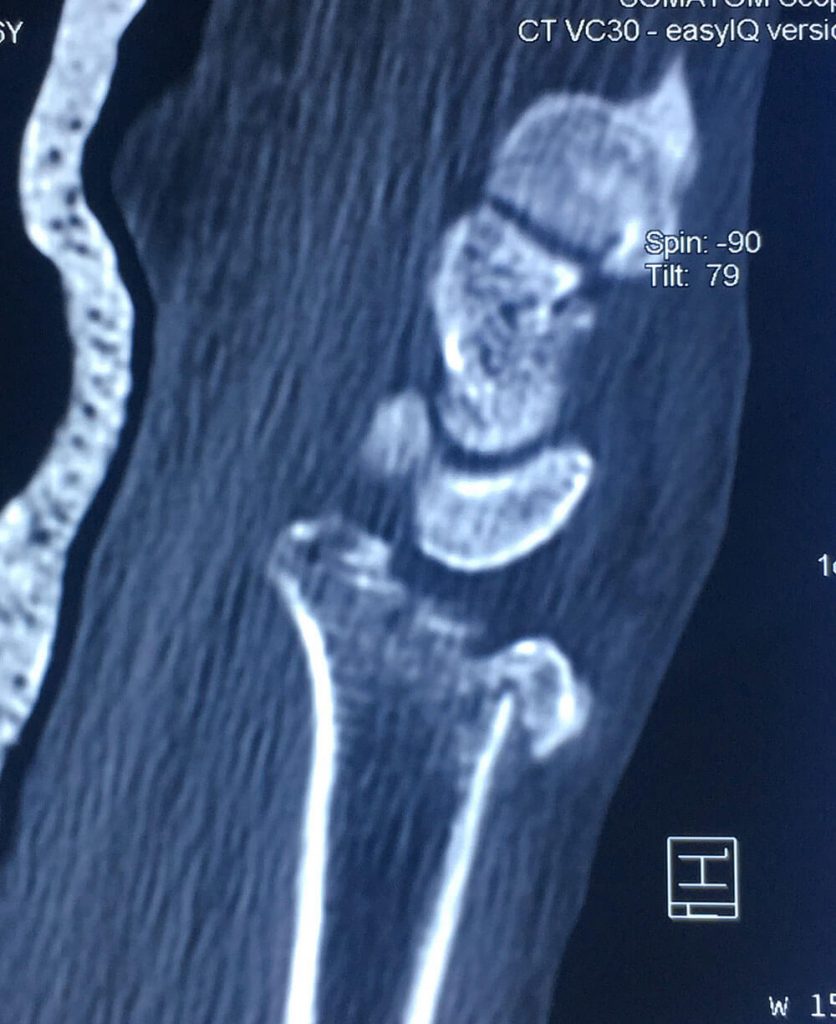

Esta radiografía del momento demostró una fractura tipo impactación de su radio dista en que la superficie articular se perdió completamente con un hundimiento central muy importante, si esto se dejara así el desarrollo de artrosis de esta articulación a corto plazo seria muy importante dejando una muñeca muy dolorosa casi para cualquier actividad, así que nos obliga a realizar una resolución quirúrgica.